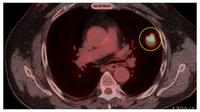

PET-CT com 18-fluordesoxiglucose (18-FDG) mostrando lesão periférica de alta captação no pulmão esquerdo. A ressecção cirúrgica confirmou câncer pulmonar de células escamosas moderadamente diferenciado

Do acervo de Dr. George Tsaknis, MD, PhD, FRCP (Londres), MRQA, MAcadMEd, PGCert; usado com permissão